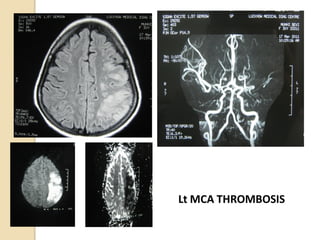

Acute ischemic stroke

 A novel application of MRA is to guide acute

stroke intervention potentially.

 MRA can be a predictor of clinical outcome in

acute ischemic pt. undergoing thrombolysis with

IV rtPA in window period. ( Marks et al 2008).

 The Boston scale ( BASIS) is a classification tool

to help predict outcomes in acute stroke by

using MRA study. ( Torres-Mozqueda et al 2008)

Lt MCA THROMBOSIS